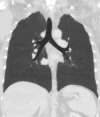

Lungs

A CT scan can be used for detecting both acute and chronic changes in the lung parenchyma, the tissue of the lungs. It is particularly relevant here because normal two-dimensional X-rays do not show such defects. A variety of techniques are used, depending on the suspected abnormality. For evaluation of chronic interstitial processes such as emphysema, and fibrosis, thin sections with high spatial frequency reconstructions are used; often scans are performed both on inspiration and expiration. This special technique is called high resolution CT that produces a sampling of the lung, and not continuous images.

Bronchial wall thickening can be seen on lung CTs and generally (but not always) implies inflammation of the bronchi.[26] Normally, the ratio of the bronchial wall thickness and the bronchial diameter is between 0.17 and 0.23.[27]

An incidentally found nodule in the absence of symptoms (sometimes referred to as an incidentaloma) may raise concerns that it might represent a tumor, either benign or malignant.[28] Perhaps persuaded by fear, patients and doctors sometimes agree to an intensive schedule of CT scans, sometimes up to every three months and beyond the recommended guidelines, in an attempt to do surveillance on the nodules.[29] However, established guidelines advise that patients without a prior history of cancer and whose solid nodules have not grown over a two-year period are unlikely to have any malignant cancer.[29] For this reason, and because no research provides supporting evidence that intensive surveillance gives better outcomes, and because of risks associated with having CT scans, patients should not receive CT screening in excess of those recommended by established guidelines.[29]